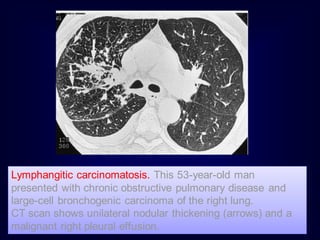

Associated pleural effusion suggests :

1.pulmonary edema

2.lymphangitic carcinomatosis

3.lymphoma

4.collagen vascular disease

Rule no. 6

Lymphangitic carcinomatosis. This 53-year-old man

presented with chronic obstructive pulmonary disease and

large-cell bronchogenic carcinoma of the right lung.

CT scan shows unilateral nodular thickening (arrows) and a

malignant right pleural effusion.